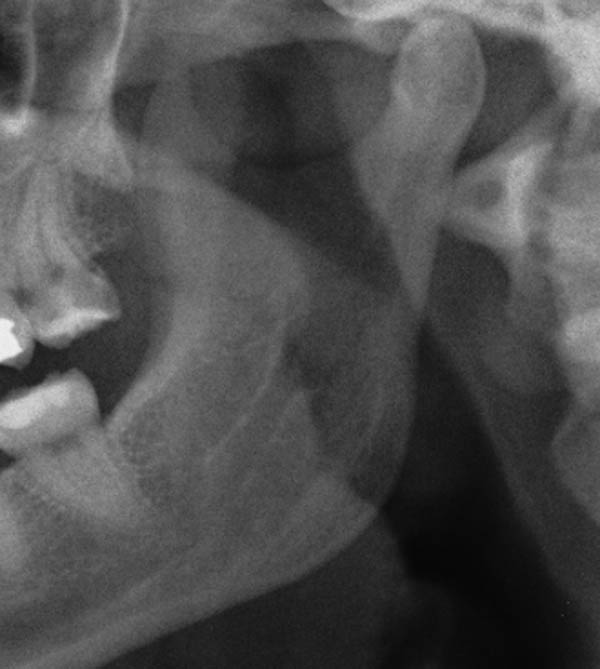

Plain X-ray Of Jaw Joint